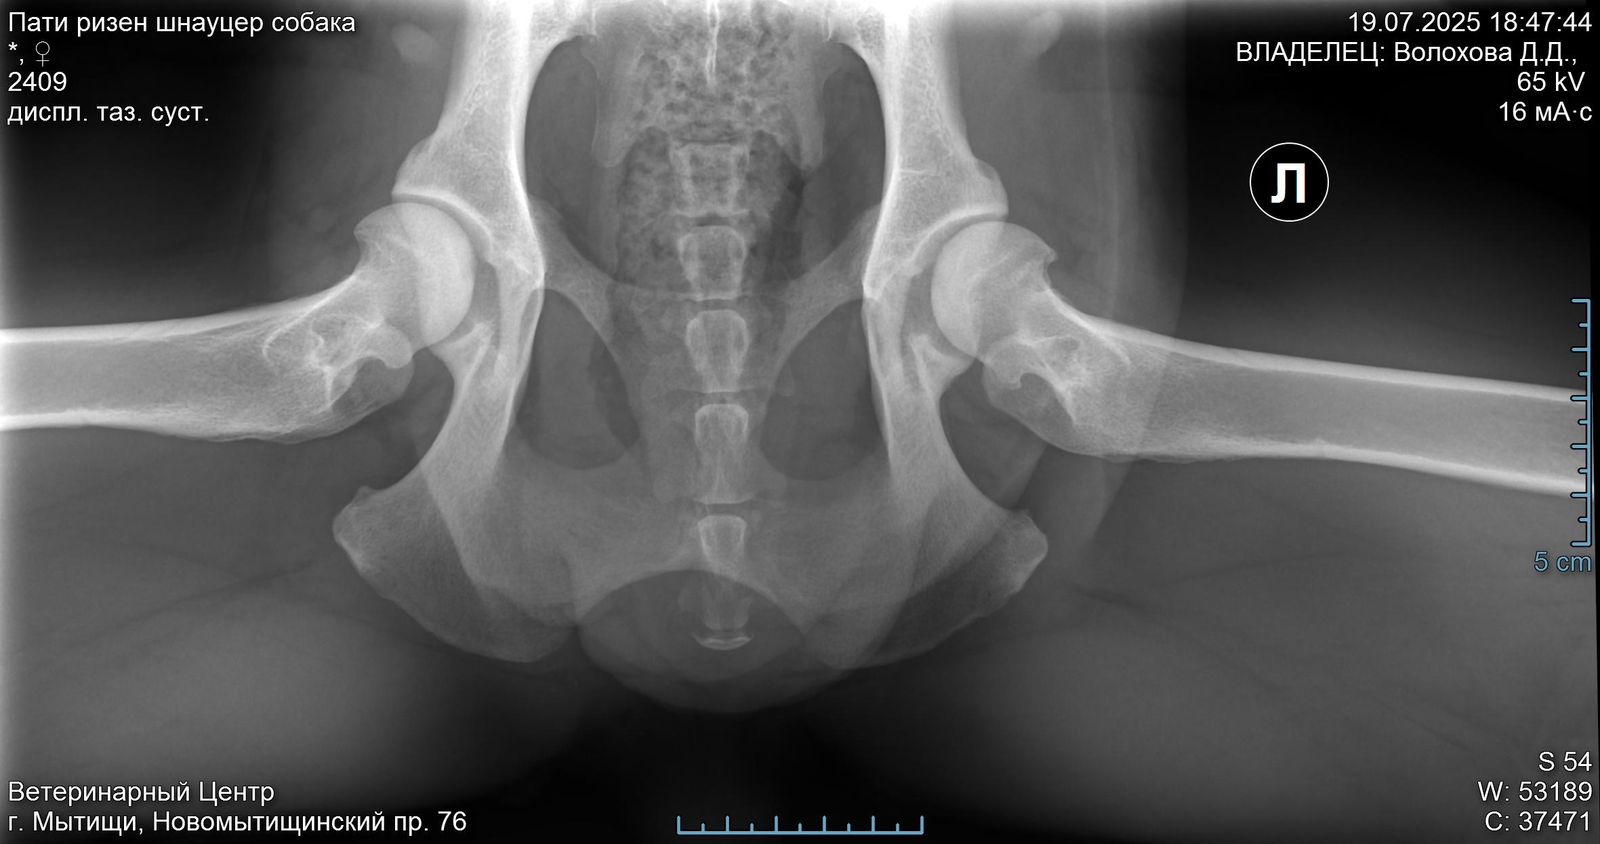

Ризеншнауцер Пати. 3 года

Задние ноги не идеал, но портить жизнь не должны.